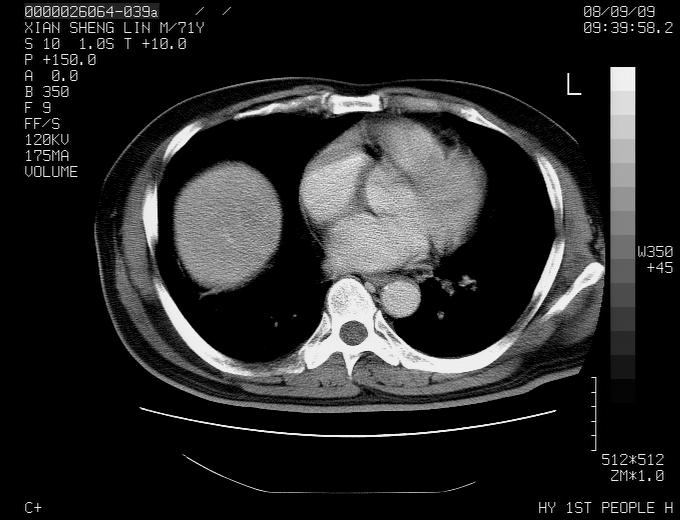

标题: CT15869:男性,71岁,因咳嗽而就诊,请讨论右上肺病变性质 [打印本页]

患者,男性,71岁,因咳嗽而就诊,

典型的右肺中心性肺癌并纵隔淋巴结转移

考虑右肺中心性肺癌并右肺门及纵隔淋巴结转移。

1,右肺中心型ca,气管隆突旁淋巴结转移。

2,右膈明显抬高,建议肝脏扫描排除转移或原发灶。